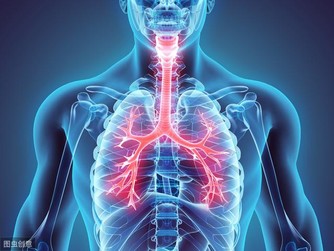

肝臟是人體代謝的重要器官, 但是肝臟發病, 很多時候是沒有明顯的癥狀表現的, 於是就讓很多人忽略了肝臟的疾病, 等到發現肝臟疾病的時候, 通常已經很嚴重了.... 因為 肝不會喊痛,等到 出血 就代誌大條了! 那要怎麼才能察覺 ???? 當我們日常生活中 出現了這幾種癥狀時,應該多留意下: 1、面色晦暗: 與太陽曬黑的皮膚不同, 該情況面部暗淡而無光澤度 另外嚴重的黑眼圈都是慢性肝病患者早期癥狀, 其中大多數為慢性B肝。 2、皮膚發黃 從未患過肝炎的人, 肝病患者早期癥狀在畏寒、發熱、 噁心、嘔吐、肝痛、極度乏力後, 忽然出現眼睛和皮膚髮黃, 則表明患了急性黃疸型肝炎; 慢性肝炎患者若出現黃疸,表明病情加重。

3、手掌心泛白 與常人的手掌顏色大不相同, 普通人的手掌顏色紅潤, 而患有肝病的病人手掌心泛白無血色。 4、蜘蛛痣 中間有一紅點,周圍有血絲狀, 類似於蚊蟲叮咬後的癥狀, 當用細棒一端壓迫痣中心時、全痣消失, 放開後又會出現, 這一肝病患者早期癥狀可與其他血管痣相鑑別。 據介紹,男性體表有蜘蛛痣者, 85%的人可有不同程度的肝臟組織病變, 其中約30%為肝硬化。 5、全身表現 身體乏力、容易疲勞是最常見的全身表現。 部分肝病患者可伴有不同程度黃疸, 表現為尿黃、眼睛黃和皮膚黃, 是最具有特異性的肝病癥狀(小兒生理性黃疸除外)。 黃疸過高時出現皮膚瘙癢。

6、消化道不適 這是最常見的肝病癥狀, 大多數肝病都會出現, 比如:噁心、厭油膩、食慾差、全身乏力等, 可出現嘔吐,腹瀉,脾腫大等癥狀。 此類癥狀也可能與慢性肝病引起的 肝原性潰瘍病, 門靜脈高壓性腸病等有關。 7、肝腹水 肝腹水一般在肝病晚期或病情極為嚴重時才會出現, 如肝硬化出現肝腹水,表示已經進入肝硬化晚期。 出血傾向: 肝病出血現象體現在肝功能減退,使凝血因子合成減少所致。 容易引起肝病患者牙齦出血、痔瘡出血、胃腸道出血等, 且出血時難以止住。 門靜脈高壓: 門脈高壓是指門靜脈係統壓力升高。 常引起食管胃底靜脈曲張,是造成消化道出血的主要原因。 一旦發生出血,結合出血傾向病情往往比較兇險, 是肝病(主要指肝硬化、肝癌晚期)死亡的主要原因之一。 8、肝性腦病 這是肝病發展到終末期的表現, 癥狀極為兇險,是造成肝病死亡最主要的原因。